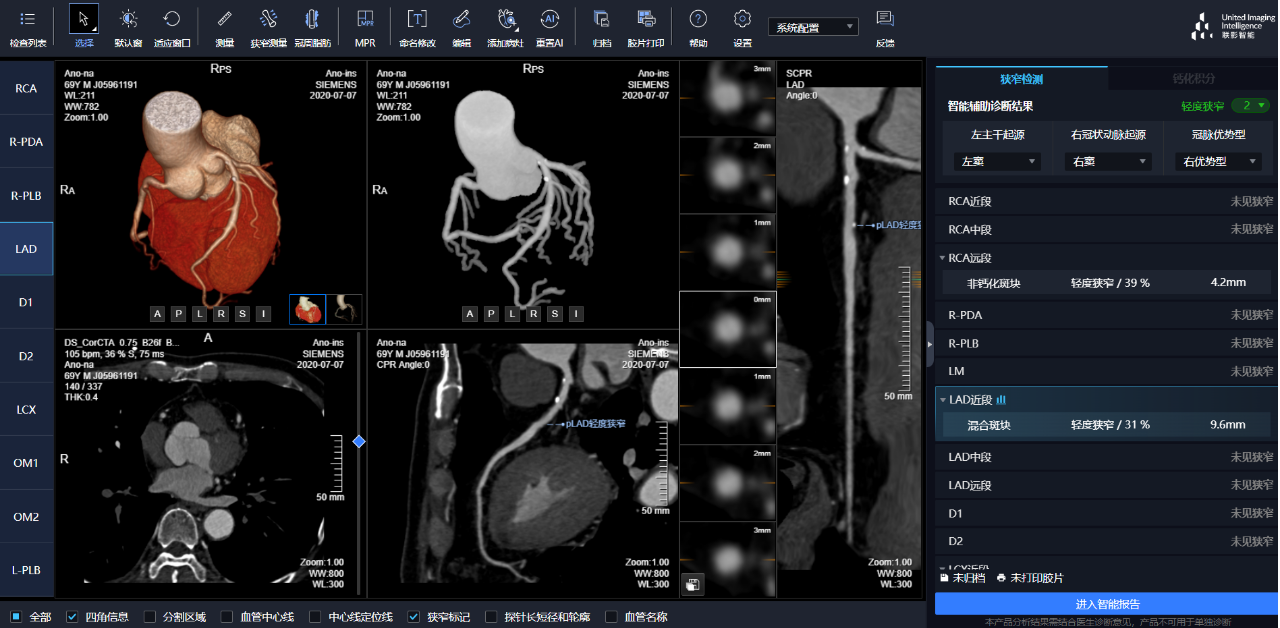

相較于傳統(tǒng)人工閱片,在聯(lián)影智能AI軟件的輔助下,640CT閱片的靈敏度和閱片效率均有顯著提升,對于細(xì)微骨折乃至于隱匿性骨折的判斷,準(zhǔn)確度更高,極大地減少了漏診及誤診。

通過3D視圖可任意旋轉(zhuǎn)觀看血管全貌,AI秒級實時計算重建血管,可實現(xiàn)多維輔診包含:板塊定性定量分析、狹窄評估、心肌橋檢出、支架檢出、鈣化積分,全程AI關(guān)注心血管健康。